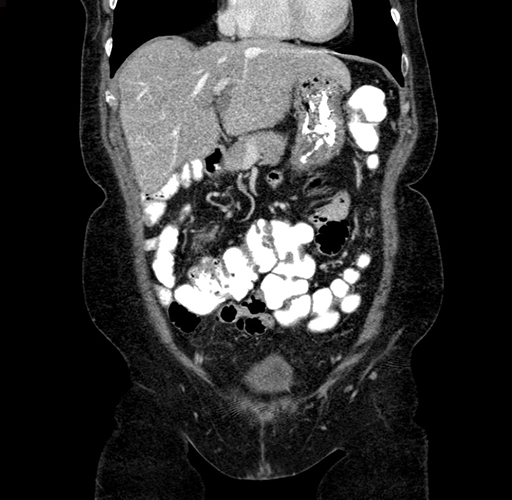

Axial Venous